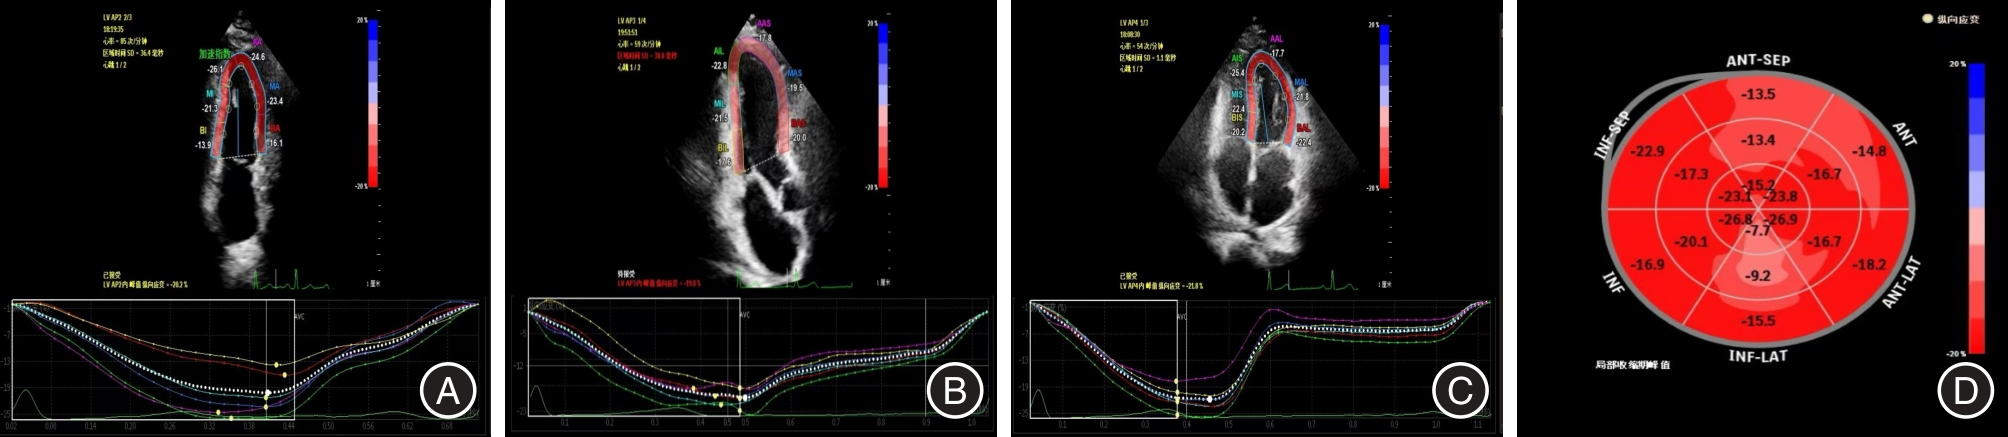

目的 应用自动心肌运动定量技术(aCMQ)评价2型糖尿病(T2DM)合并肾功能不全(CKD)患者的左室收缩功能并探讨其与临床生化指标的相关性。 方法 纳入80例T2DM患者,分为DM组(不合并CKD,n = 40)和DN组(合并CKD,n = 40),另外选取40例健康志愿者作为对照组,记录所有受试者的一般临床资料,并且行常规超声心动图和aCMQ技术检查,获取常规超声测量值和 aCMQ相关参数。 结果 aCMQ相关参数比较:三组左室整体纵向应变(LVGLS)、左室心尖两腔心纵向应变(LVAP2LS)、左室心尖三腔心纵向应变(LVAP3LS)、左室心尖四腔心纵向应变(LVAP4LS)差异均有统计学意义(P < 0.05)。DN组左室整体环向应变(LVGCS)与另外两组相比差异均有统计学意义(P < 0.05)。左室短轴基底段环向应变(LVSAXBCS)、左室短轴中间段环向应变(LVSAXMCS)、左室短轴心尖段环向应变(LVSAXACS)差异均无统计学意义(P > 0.05)。左室应变参数与高敏C反应蛋白(hs-CRP)、糖化白蛋白(GA)、糖化血红蛋白、肌酐、尿素及尿酸呈负相关,而与肾小球滤过率(eGFR)呈正相关。其中hs-CRP、GA和eGFR与左室应变参数之间有较好的相关性。 结论 aCMQ技术可早期发现T2DM合并CKD患者左室功能的恶化,通过左室应变参数与hs- CRP、GA和eGFR的相关性有助于更好地评估其心脏受累情况。

Objective To evaluate the left ventricular systolic function of patients with type 2 diabetes mellitus (T2DM) combined with renal insufficiency (CKD) by applying automated myocardial motion quantification (aCMQ) and to investigate its correlation with clinical biochemical indexes. Methods 80 patients with T2DM were enrolled, divided into DM group (without CKD, n = 40) and DN group (with CKD, n = 40), and 40 healthy volunteers were selected as the control group. The general clinical data of all subjects were recorded, and routine echocardiography and aCMQ were performed to obtain routine ultrasonographic measurements and aCMQ-related parameters. Results Comparison of aCMQ-related parameters: The differences in LV global longitudinal strain (LVGLS), LV apical 2-chamber longitudinal strain (LVAP2LS), LV apical 3-chamber longitudinal strain (LVAP3LS), and LV apical 4-chamber longitudinal strain (LVAP4LS) among the three groups were all statistically significant (P < 0.05). The differences in LV global circumferential strain (LVGCS) between the DN group and the other two groups were statistically significant (P < 0.05). The differences in LV short-axis basal segment cyclic strain (LVSAXBCS), LV short-axis middle segment cyclic strain (LVSAXMCS), and LV short-axis apical segment cyclic strain (LVSAXACS) were not statistically significant (P > 0.05). LV strain was negatively correlated with Hs- CRP, GA, HbA1c, creatinine, urea, and uric acid, and positively correlated with eGFR. Correlation. High-sensitivity C-reactive protein (Hs-CRP), glycated albumin (GA) and eGFR showed good correlation with LV strain parameters. Conclusion The aCMQ technique can detect the deterioration of left ventricular function in patients with type 2 diabetes mellitus combined with renal insufficiency at an early stage, and the correlation between left ventricular strain parameters and hs-CRP, GA and eGFR can help to better assess their cardiac involvement.